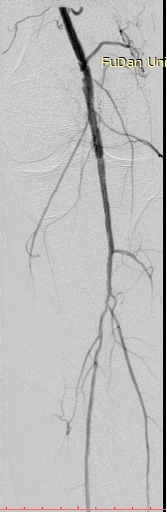

病例-1 男性,77岁,左下肢SFA支架术后7年,旁路术后3年静息痛 ABI:左侧 0.35